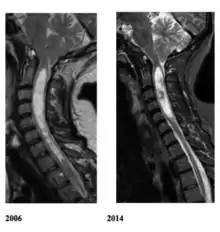

La siringomielia es un trastorno en el cual se forma un quiste dentro de la médula espinal. Este quiste se conoce como siringe o syrinx. Con el tiempo, el syrinx se expande y alarga, destruyendo el centro de la médula espinal. Puesto que la médula espinal conecta el cerebro con los nervios de las extremidades, este daño causa dolores, debilidad y rigidez en la espalda, los hombros, los brazos o las piernas. Otros síntomas pueden incluir dolores de cabeza (cefalea) y pérdida de la capacidad de sentir calor o frío extremos, especialmente en las manos. Cada paciente tiene una combinación distinta de síntomas.

Cerca de 21 000 personas en Estados Unidos sufren de siringomielia. Otras enfermedades comparten los síntomas iniciales de la siringomielia. En el pasado, esto ha dificultado el diagnóstico. Sin embargo, con la resonancia magnética nuclear ha aumentado notablemente el número de casos de siringomielia diagnosticados en las etapas iniciales del trastorno.

Una serie de lesiones pueden obstruir el flujo normal del líquido cefalorraquídeo y redirigirlo hacia la médula espinal. Esto da lugar a la formación del syrinx o siringe, el cual se llena de líquido cefalorraquídeo. Las diferencias de presión a lo largo de la médula espinal hacen que el líquido se mueva dentro del quiste. Se cree que este movimiento continuo del líquido da lugar al crecimiento del quiste y causa daños adicionales a la médula espinal.

La mayoría de los síntomas se deben a la lesión irreversible del tejido nervioso, y este no es capaz de reemplazarlo; sin embargo, parece ser que en la siringomielia idiopática la sección del filum terminale detiene la enfermedad.[4] El quiste resultado de la necrosis celular queda igual, pero puede desaparecer cuando espontáneamente se abre el espacio que rodea la médula espinal o lo hace hacia el centro de ella donde existe un conducto, el conducto ependimario, que comunica el centro de la médula con las cavidades cerebrales.